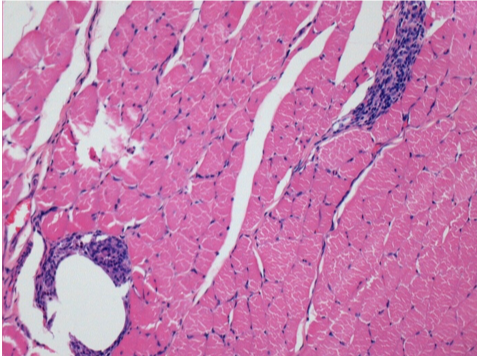

10 días después de la inyección de Endopeel

10 días después de la inyección de Endopeel 0,1 ml en el músculo pretibial derecho.

Aquí puede ver la formación de las vacuolas que están rodeadas de linfocitos. Las vacuolas son diferentes a la necrosis tisular. La presencia de linfocitos está relacionada con la permeabilidad de las membranas celulares.

L : Control-100xD10

R:100xD10

R :200xD10

R :400xD10